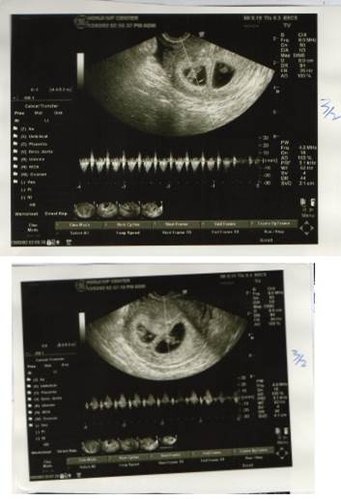

在宏孕诊所第一次我只取到二颗卵,置放5天,一颗为囊胚A级,一颗为B级,玻璃冷冻后,进行第二次疗程,这次取到3颗卵,2颗空包蛋,另1颗的品质似乎不如上次的2颗,因此,我决定植入上次的2颗,很顺利的2颗胚胎都顺利著床,也都有心跳。不过,我想此次成功原因也或许是因为我刺激的卵数少,卵子们能有较多的养分、品质较好有关,不过我想这就交给专家们去研究了!